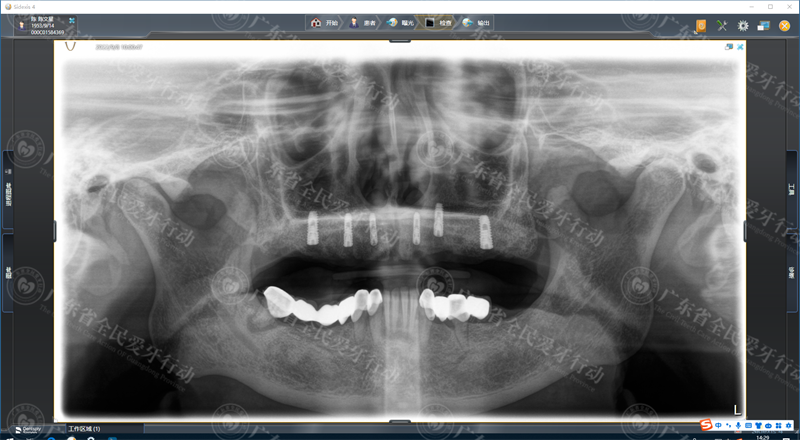

术前CT:上颌牙缺失严重,多残根烂牙

术前CT:上颌种植6颗种植牙,恢复上半口牙

陈伯的上颌蛀牙残根、松动牙,需要全部拔除,重新种牙治疗。陈伯表示理解:“烂牙坏牙不换掉它,会影响嘛。要配合医生来治疗来搞。”

经过详细的数字化拍片检查,专家为陈伯制定了一套既能减少种牙时间,又能更快恢复半口好牙的方案——利用全智能精控种植“all-on-6”上面植入6颗种植体,恢复稳固半口上颌好牙。